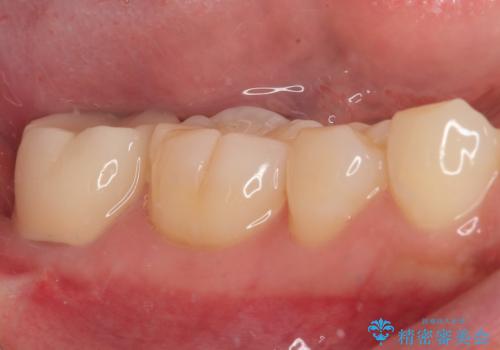

親知らず抜歯の症状が治まってから手前の歯の状態を確認しましたが、特に症状は認められませんでした。

それでも生活歯髄療法になる可能性を考慮して、ラバーダム装着下にてむし歯を除去し、神経組織が露出寸前であったためMTAセメントによる歯随保護を行いました。

処置後神経の反応が正常であることを確認して、オールセラミッククラウンを装着しました。